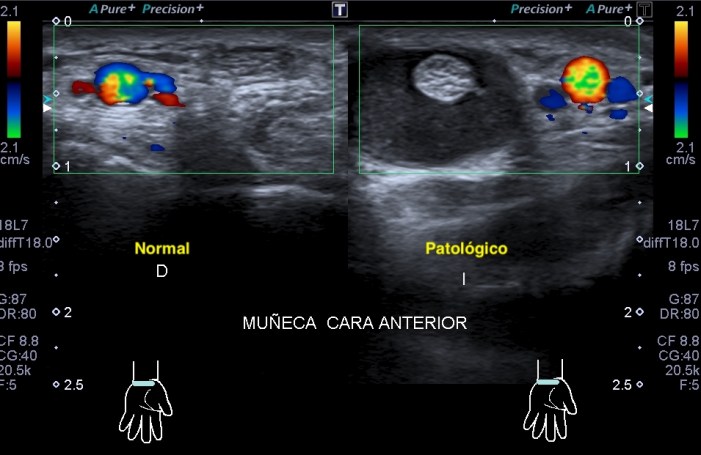

309. Afectación del Nervio Mediano

Paciente que acude por corte en la región anterior y central de la muñeca.

Después de 20 días nota parestesias en los dedos. La herida está cicatrizada, pero el movimiento es limitado.

Voy a tratar de explicarte en 4 imágenes los hallazgos para que veas la complejidad del caso, de la anatomía y de la exploración ecográfica de la cara anterior del la muñeca.

Primero necesitamos conocer bien la anatomía de esa región. En la parte central de la muñeca el nervio mediano ya se ha situado por encima de los tendones flexores de la muñeca que luego se convertirán en en los músculos flexores de la cara anterior del antebrazo, previamente en nervio mediano, más en la muñeca, a distal, es mas profundo y radial.

En el lugar del corte el nervio mediano es muy superficial antes de hacerse más profundo entre la musculatura flexora superficial y profunda del antebrazo anterior. Ahí donde más expuesto está es donde se produce el corte que estudiado en eje largo nos ofrece esta imagen preciosa, mira:

En la imagen aprecias claramente como la superficie de la muñeca está afectada por un tejido cicatricial, fibroso, heterogéneo, típico de una herida de reciente curación.

Más profundo el nervio mediano, comprimido por la fibrosis y claramente afectado en esta localización en su parte más superficial. Así mismo y fruto de la presión ejercida en capas, el flexor, más pequeño y cóncavo bajo el tejido neuronal afectado. Claramente afectación de las dos primeras capas.

Sin embargo en este vídeo del perfil de María Leal puede comprobar perfectamente como el flexor desliza perfectamente bajo el nervio, que funcionalmente normal, no se mueve con la flexión de los dedos..

Explicarte estos cambios individualizadamente es complicado a sí que voy a usar la comparativa de normalidad y patología de amabas muñecas y vas a poder ver como cambia el aspecto, las medidas tanto en milímetros como en áreas.

Mira:

Observa las medidas, observa en esta imagen superior el Retináculo afectado, engrosado, hiperecogénico.

Como en las últimas 3 imágenes comparativas puedes ver perfectamente la afectación local, pero en esta imagen final que tienes arriba justo, ves la afectación global de todas la ecoestrusturas que componen la anatomía locorregional.

El proceso cicatrizador afectando al nervio y a las partes blandas es evidente, muy plástico, uno de lo estudios más bonitos que he hecho, con la calidad de la imagen de CANON MEDICAL.